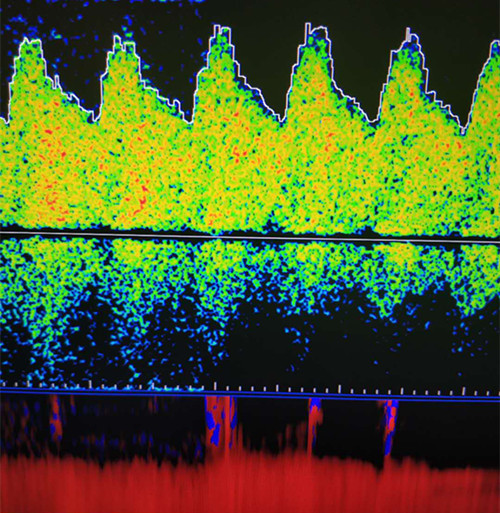

前循環(huán)動(dòng)脈低波動(dòng)表現(xiàn)